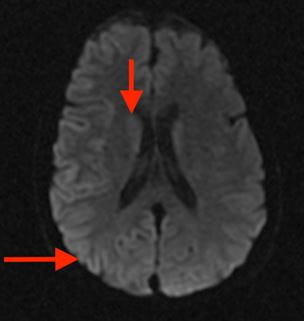

When Proteins Go Rogue: The Prion Paradigm in Neurodegenerative Disease

Neuropsychiatrist Brian Appleby, MD, shares insights on prion diseases like Creutzfeldt-Jakob and UH’s groundbreaking research and trials to better understand these rare but fatal neurodegenerative disorders.

UH is First Site Activated in Groundbreaking Global Prion Disease Treatment Trial